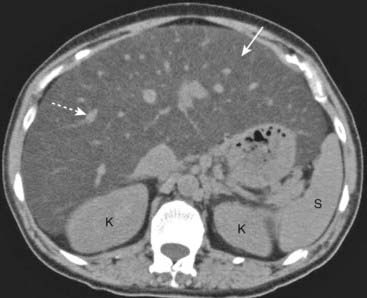

Figure 18-26 Triple-phase CT scan of the liver, hepatocellular carcinoma.

Evaluation of liver masses is usually done with a combination of scans including an unenhanced scan (A) and then two postcontrast scans: one obtained quickly (hepatic-arterial phase) (B) and a second (portal-venous phase) slightly delayed (C). The combination of three scans is called a triple-phase scan. This case shows the typical findings of a focal hepatocellular carcinoma. Most are low density (hypodense) or the same density as normal liver (isodense) without contrast (solid white arrow in A), enhance on the arterial phase with IV contrast (hyperdense) (dotted white arrow in B) and then return to hypodense or isodense on the venous phase (dashed white arrow in C).